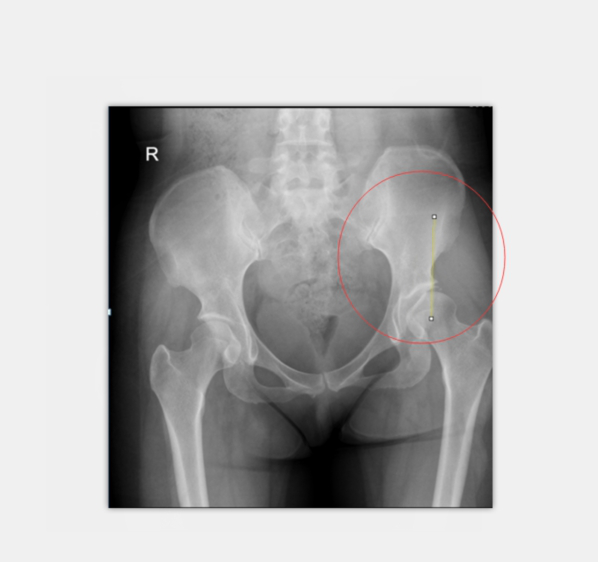

術(shù)前X光:患者左髖臼CE角約0度

診斷考慮:先天性髖臼關(guān)節(jié)發(fā)育不良